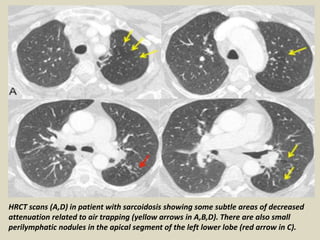

HRCT scans (A,D) in patient with sarcoidosis showing some subtle areas of decreased

attenuation related to air trapping (yellow arrows in A,B,D). There are also small

perilymphatic nodules in the apical segment of the left lower lobe (red arrow in C).